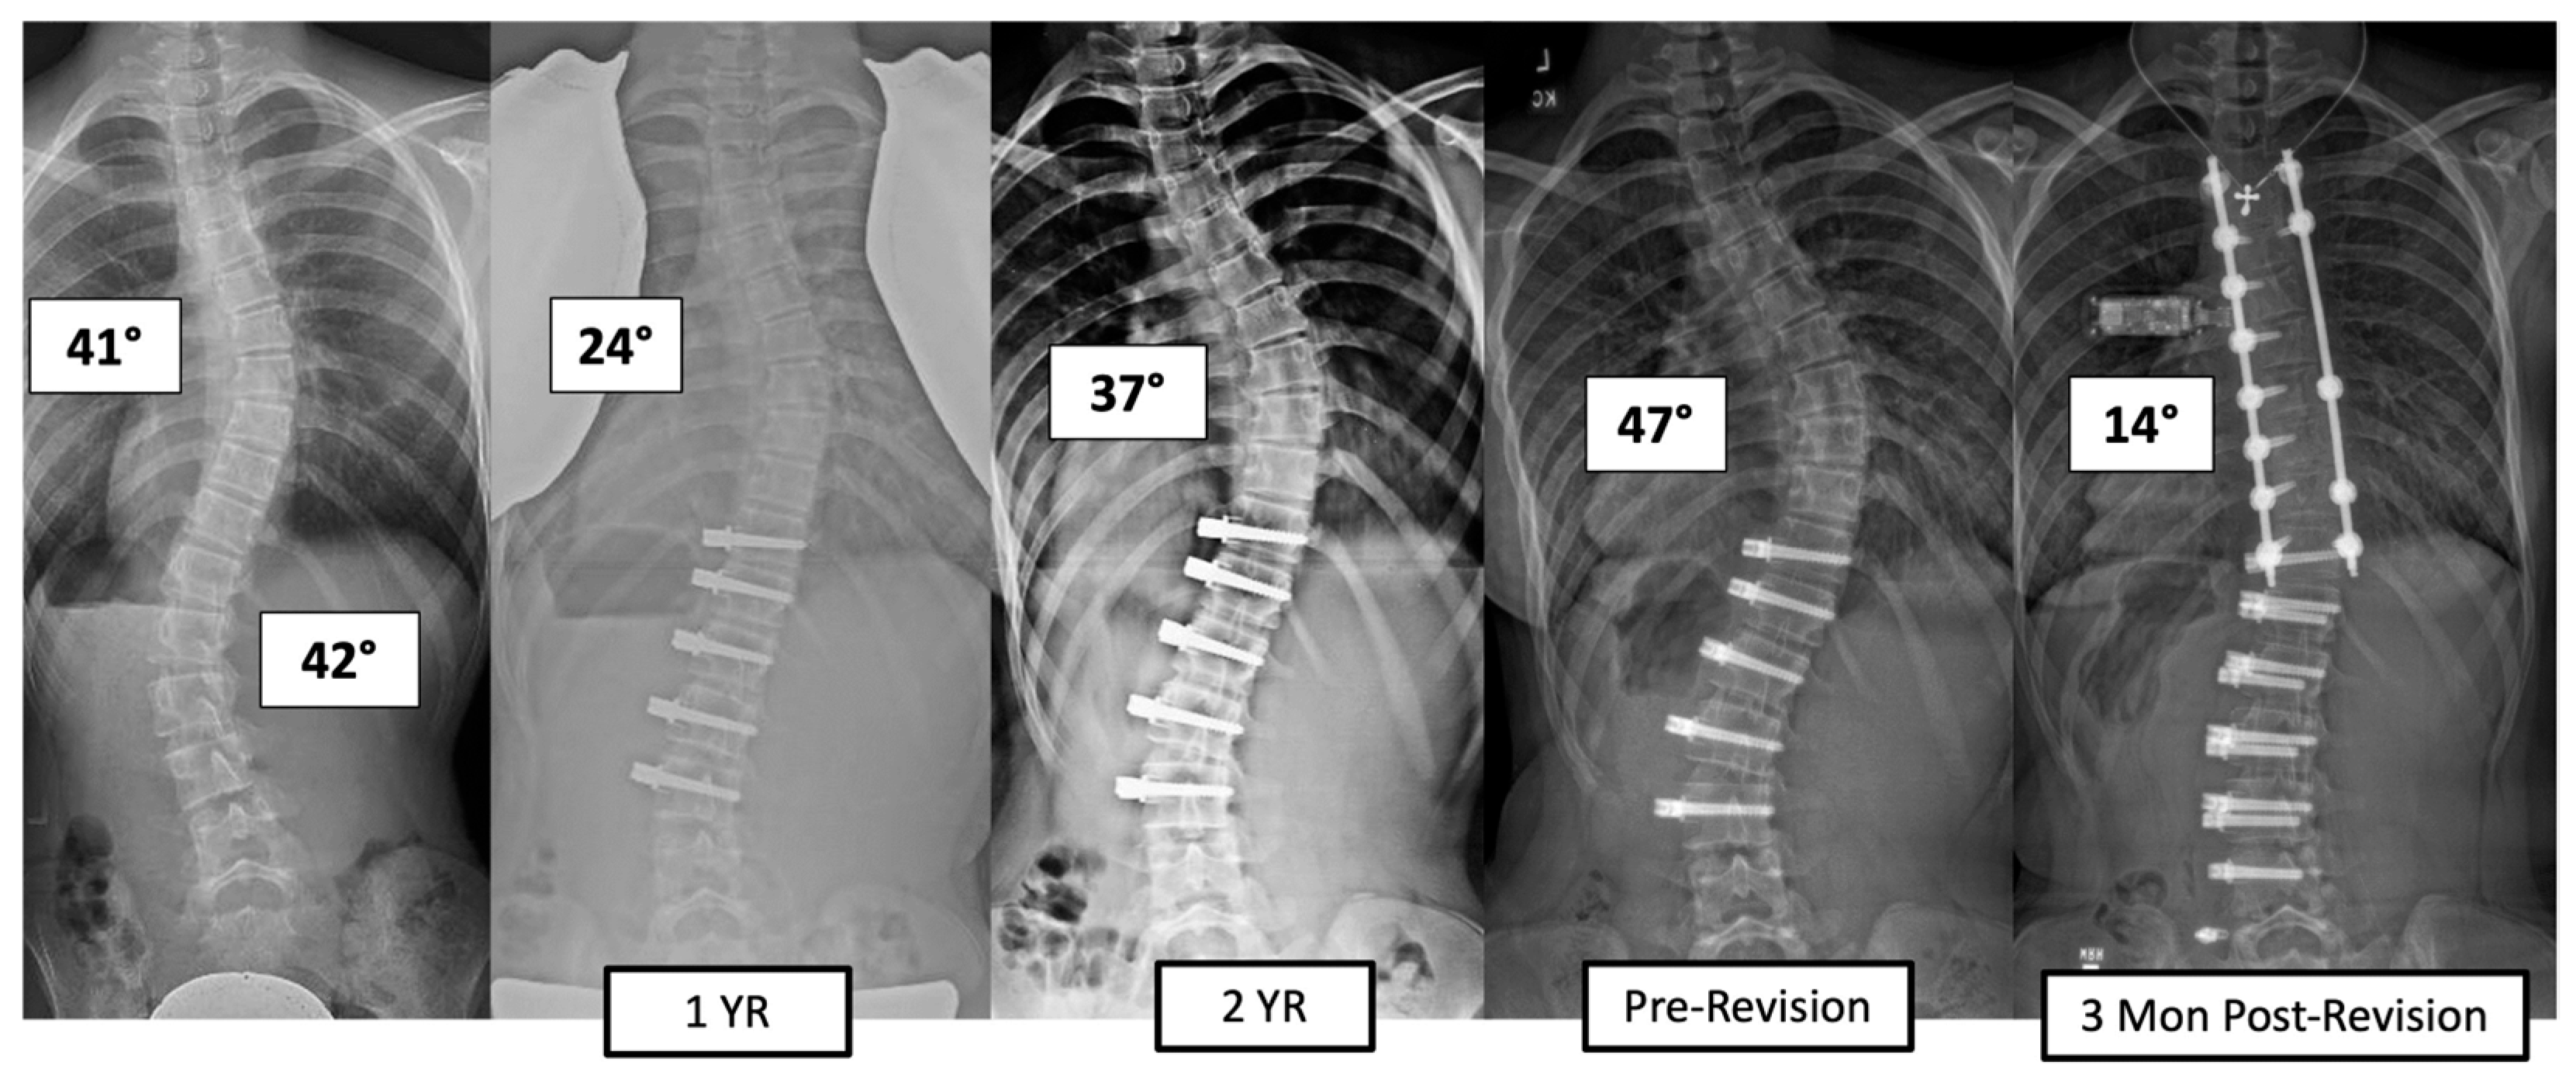

There were four major complications (10.8%), including one readmission and three patients who required re-operation. Patient 1 underwent re-operation due to radiculopathy caused by a screw tip impinging on a nerve root in a lumbar foramen requiring screw revision and replacement of the tether. At 3 years post operation, they have a broken tether at one level, but no further revision is needed. Patient 2 had progression of a previously uninstrumented thoracic minor curve which progressed following lumbar tether breakage. This was revised with fusion of the previously untreated thoracic curvature and the addition of a second row of screws and second tether for the thoracolumbar construct (Figure 3). Patient 3 had overcorrection of the thoracolumbar curvature and adding on of the thoracic. As a result, the tether was released in the thoracic region and the thoracolumbar tether was revised (Figure 4). One patient (3%) required readmission due to an inability to tolerate post-operative pain medication. During admission, pain was controlled, and they were discharged without sequela.

Figure 3.

This is a 13-year-old female who experienced progression of the thoracic curve following tether breakage in the lumbar spine. The patient was revised with fusion of the previously untreated thoracic curvature and addition of a second row of screws and second tether for the thoracolumbar construct.

The incidence of TB in the literature has ranged widely (27–73%) and may be even higher as we typically rely on radiographic evidence of breakage [3,4,14,15]. Our TB rate of 49% is consistent with what has been reported in the thoracic VBT literature but lower than what has been reported for lumbar curvatures [3,4]. Baroncini et al. performed an analysis of 105 patients (69 lumbar curves; 84 thoracic curves) who experienced early TB (within 1 year of the index procedure). Of those who experienced breakage, there was a higher incidence amongst lumbar curves (71%) than thoracic (29%) [23]. They suspected that this was due to either the greater range of motion in the lumbar spine or differences in orientation of the facet joints between the thoracic and lumbar spine. In a study on the Lenke 6 curve type, there has been support for bilateral VBT in achieving a significant correction of T and TL curves at a minimum of 24 months post operation [24]. Although TB and loss of correction have been observed, breakage while associated with a segmental loss of correction does not necessarily require re-operation or result in a lack of clinical success (major curve <35%) [1,4,14]. Of the 18 patients in our cohort who experienced TB, 15 (83%) were still clinically successful. Previously, we found a 30% breakage rate of thoracolumbar tethers at the 2-year time point, suggesting that rates increase over time given our 49% rate at 3–6 years [14]. Tether breakage does not appear to be associated with a high revision rate, at least out to the length of the follow-up we report. Of the patients who have been revised in this series (8.1% rate), only one patient who had tether breakage required a revision related to curve progression. This was in a patient in whom a TL tether was performed, breakage occurred, and moderate progression of the TL major curve occurred along with progression of the secondary thoracic curve. This was treated with posterior fusion of the thoracic spine and revision of the TL tether (Figure 3). The interplay between the number of cords and skeletal maturity in outcome durability will require larger data sets. The authors have tended to use single-cord constructs in the lumbar spine when the patient had not yet reached peak height velocity with the expectation that growth modulation would drive correction and maintenance, and a double cord might lead to overcorrection due to a more powerful convex tethering force [25]. The authors routinely use double-row cords for TL major curves for patients who have surpassed peak height velocity and/or patients with curves >60 degrees, regardless of skeletal maturity.